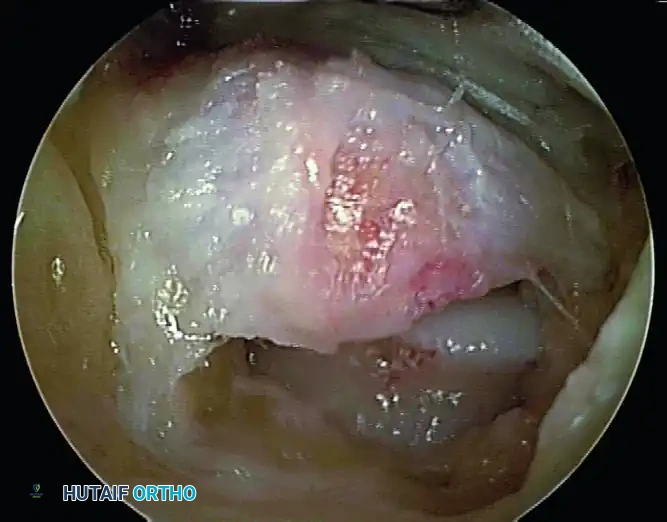

Step 1: Soft Tissue Clearance and Capsulectomy

Introduce a 4.0-mm or 4.5-mm full-radius arthroscopic shaver into the posteromedial portal. Begin by resecting the adipose tissue and the posterior subtalar capsule to clear the visual field.

Step 2: Identification of the FHL Tendon

Before any bony resection occurs, the flexor hallucis longus (FHL) tendon must be positively identified. Use the shaver or a radiofrequency wand to carefully clear the soft tissue overlying the FHL muscle belly and tendon. The FHL will be seen gliding dynamically if the great toe is passively flexed and extended by an assistant.

Pitfall: Failure to identify the FHL early in the procedure leads to spatial disorientation. The FHL is the medial boundary; all pathology to be resected (os trigonum, Stieda process) lies lateral to this structure.

Step 3: Excision of the Os Trigonum / Stieda Process

Once the FHL is protected, direct attention to the bony impingement. To mobilize and remove the os trigonum, you must systematically detach its soft tissue tethers:

1. Partially detach the posterior talofibular ligament (PTFL).

2. Release the posterior talocalcaneal ligament.

3. Release the flexor retinaculum to fully expose the bony fragment.

Use an arthroscopic grasper to assess the mobility of the os trigonum. If it is fused (a Stieda process), use an arthroscopic burr or an osteotome to resect the prominent bone until it is flush with the posterior talar body. If it is a separate ossicle, use a combination of a shaver, radiofrequency wand, and grasper to shell it out of its soft tissue envelope. Extract the fragment through the portal; if the fragment is large, the portal skin incision may need to be slightly enlarged.